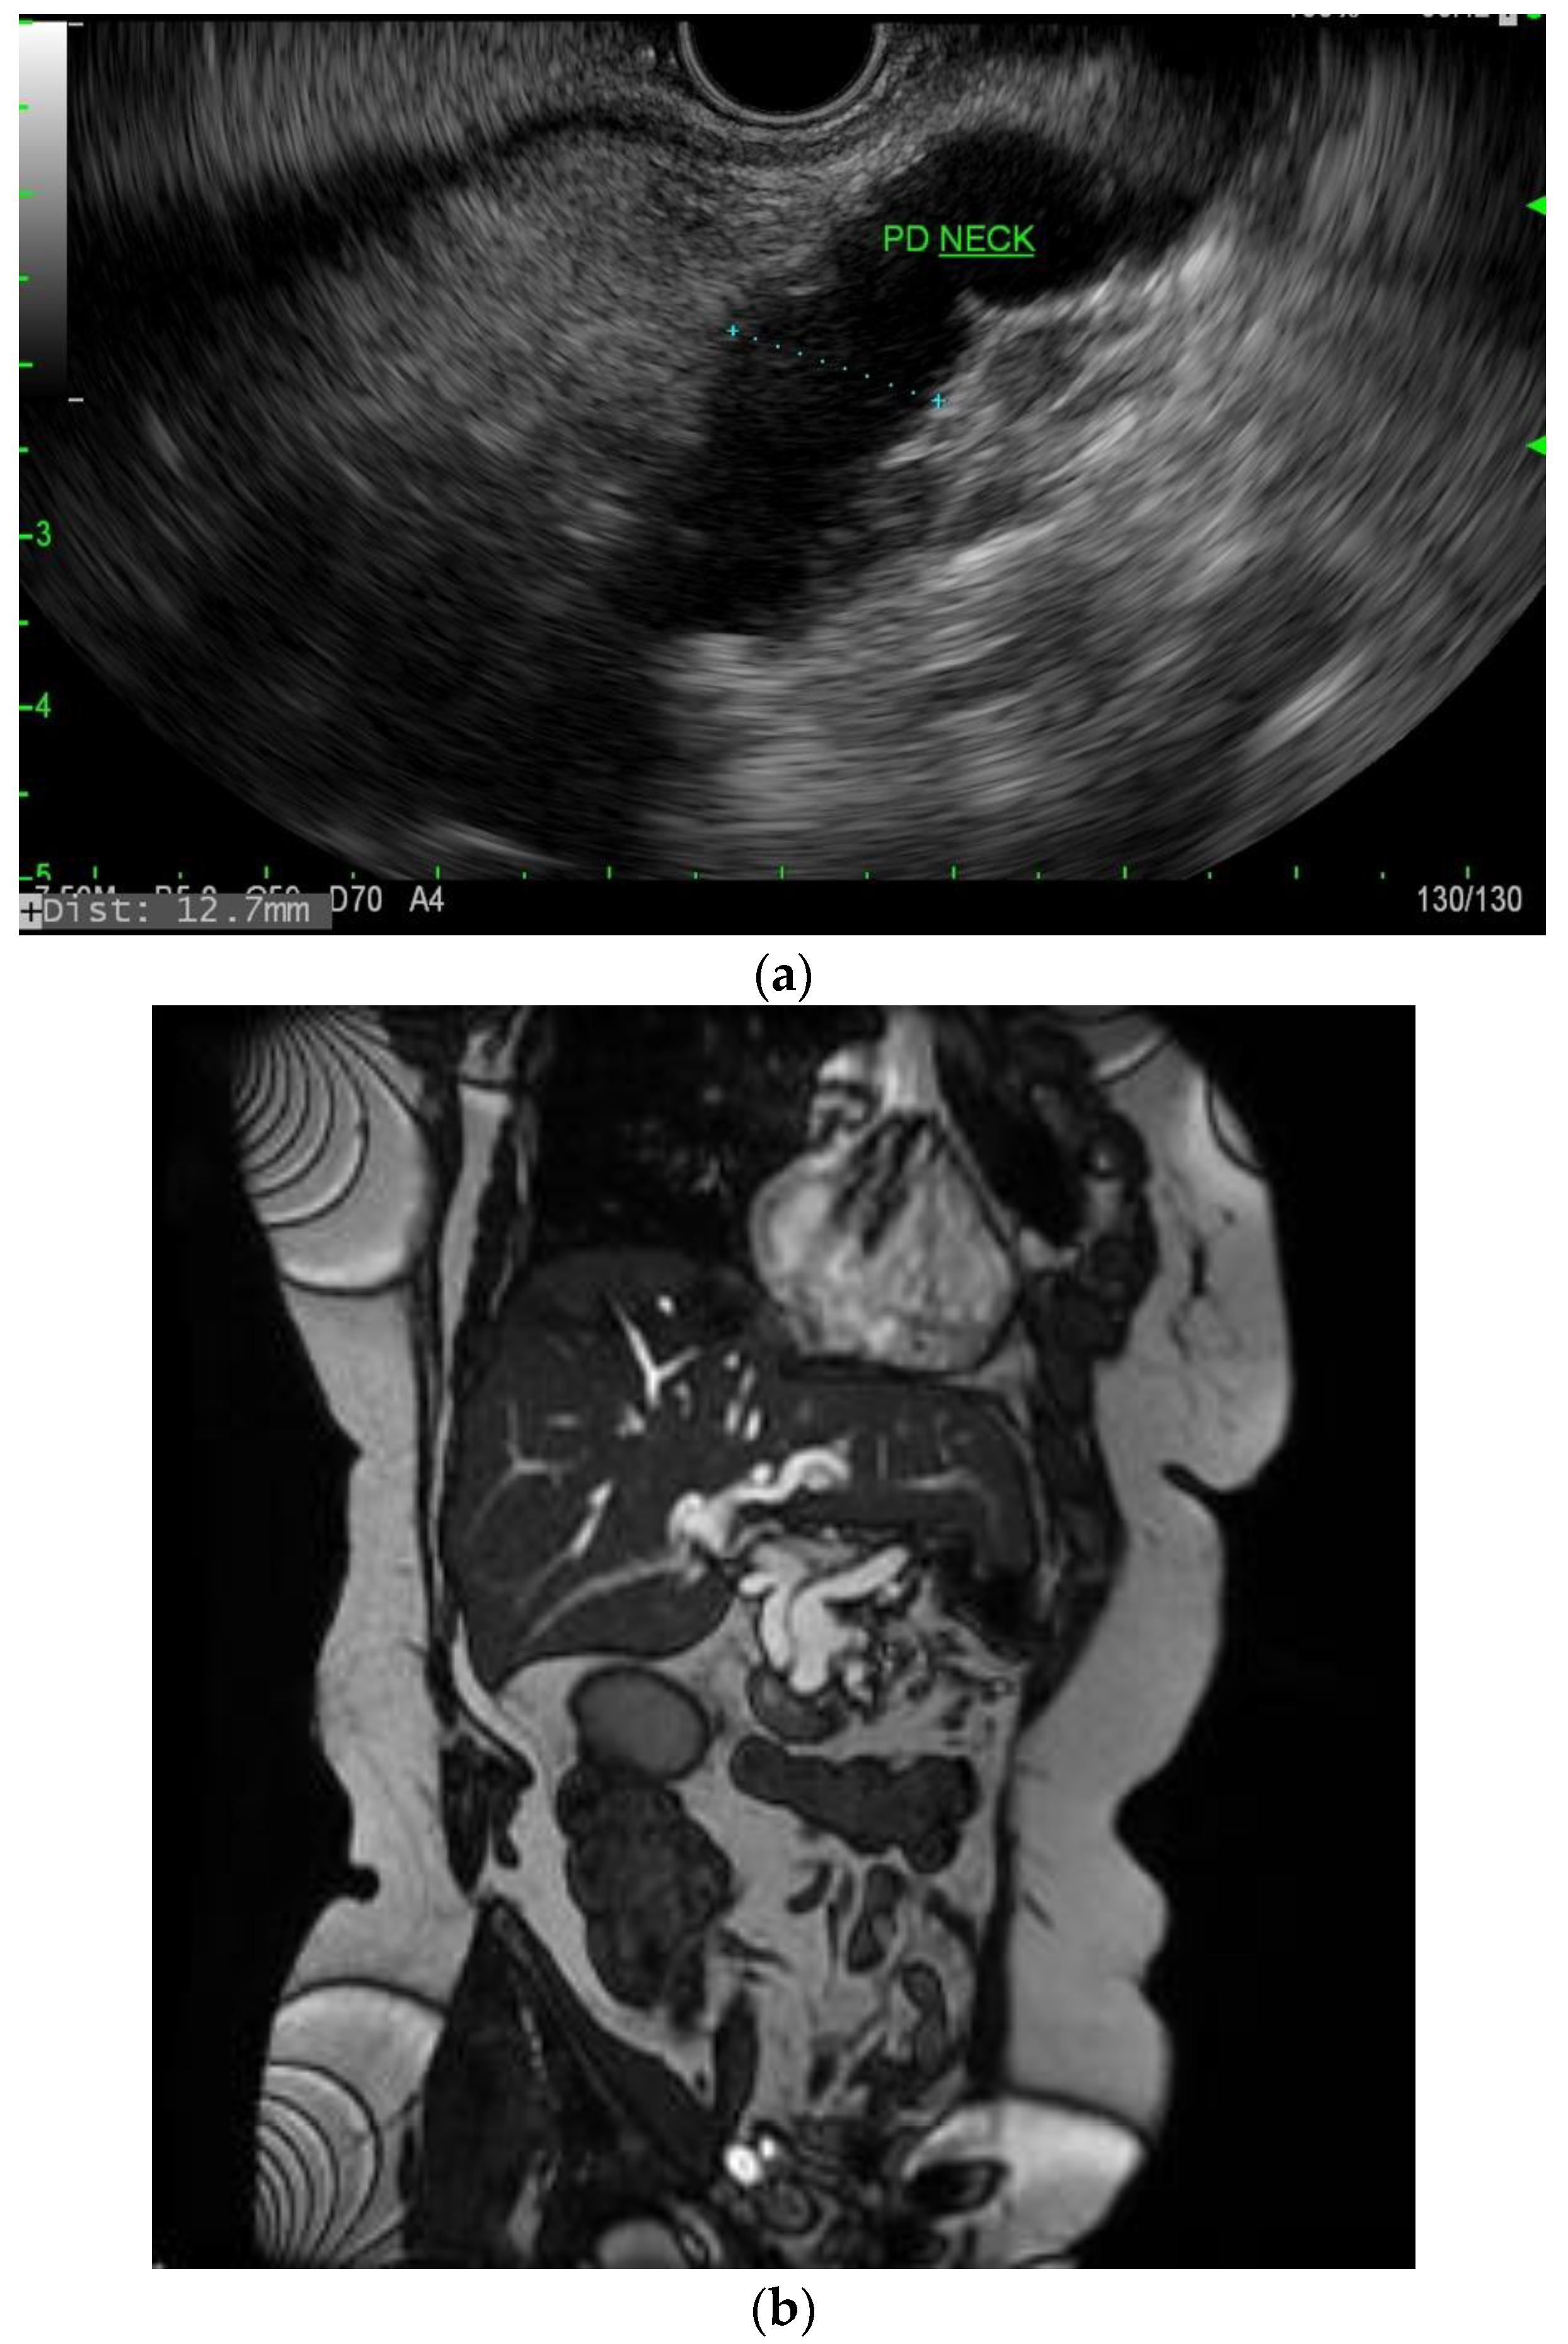

IPMNs can be divided into main duct intraductal papillary mucinous neoplasm and branch duct intraductal papillary mucinous neoplasms, with dilation of the main pancreatic duct helping to distinguish between the two. They usually present in the fifth to seventh decade of life and have an equal distribution between males and females [15]. Intraductal neoplasms are typically associated with a dilated main pancreatic duct (Figure 2a,b), whereas the branch duct IPMNs are associated with a dilated pancreatic duct branch or branches (Figure 3). A mixed IPMN is defined as a cystic lesion with ductal communication and main pancreatic duct dilation greater than or equal to 5 mm (Figure 4). Diabetes mellitus (DM) and a family history of pancreatic adenocarcinoma are known risk factors for IPMN, with odds ratios of 1.79 (CI 95%: 1.08–2.98) and 2.94 (CI 95%: 1.17–7.39), respectively [16]. Cytology can show columnar cells with variable atypia and can stain positive for mucin. CEA is usually greater than 200 ng/mL in approximately 75% of lesions, similar to mucinous neoplasms. Main duct IPMNs have a 36–100% risk of malignant potential, compared to a lower risk of 11–30% malignant potential of side branch IPMNs [17].

Figure 2.

(a) EUS image of main duct IPMN; (b) MRI image of main duct IPMN.